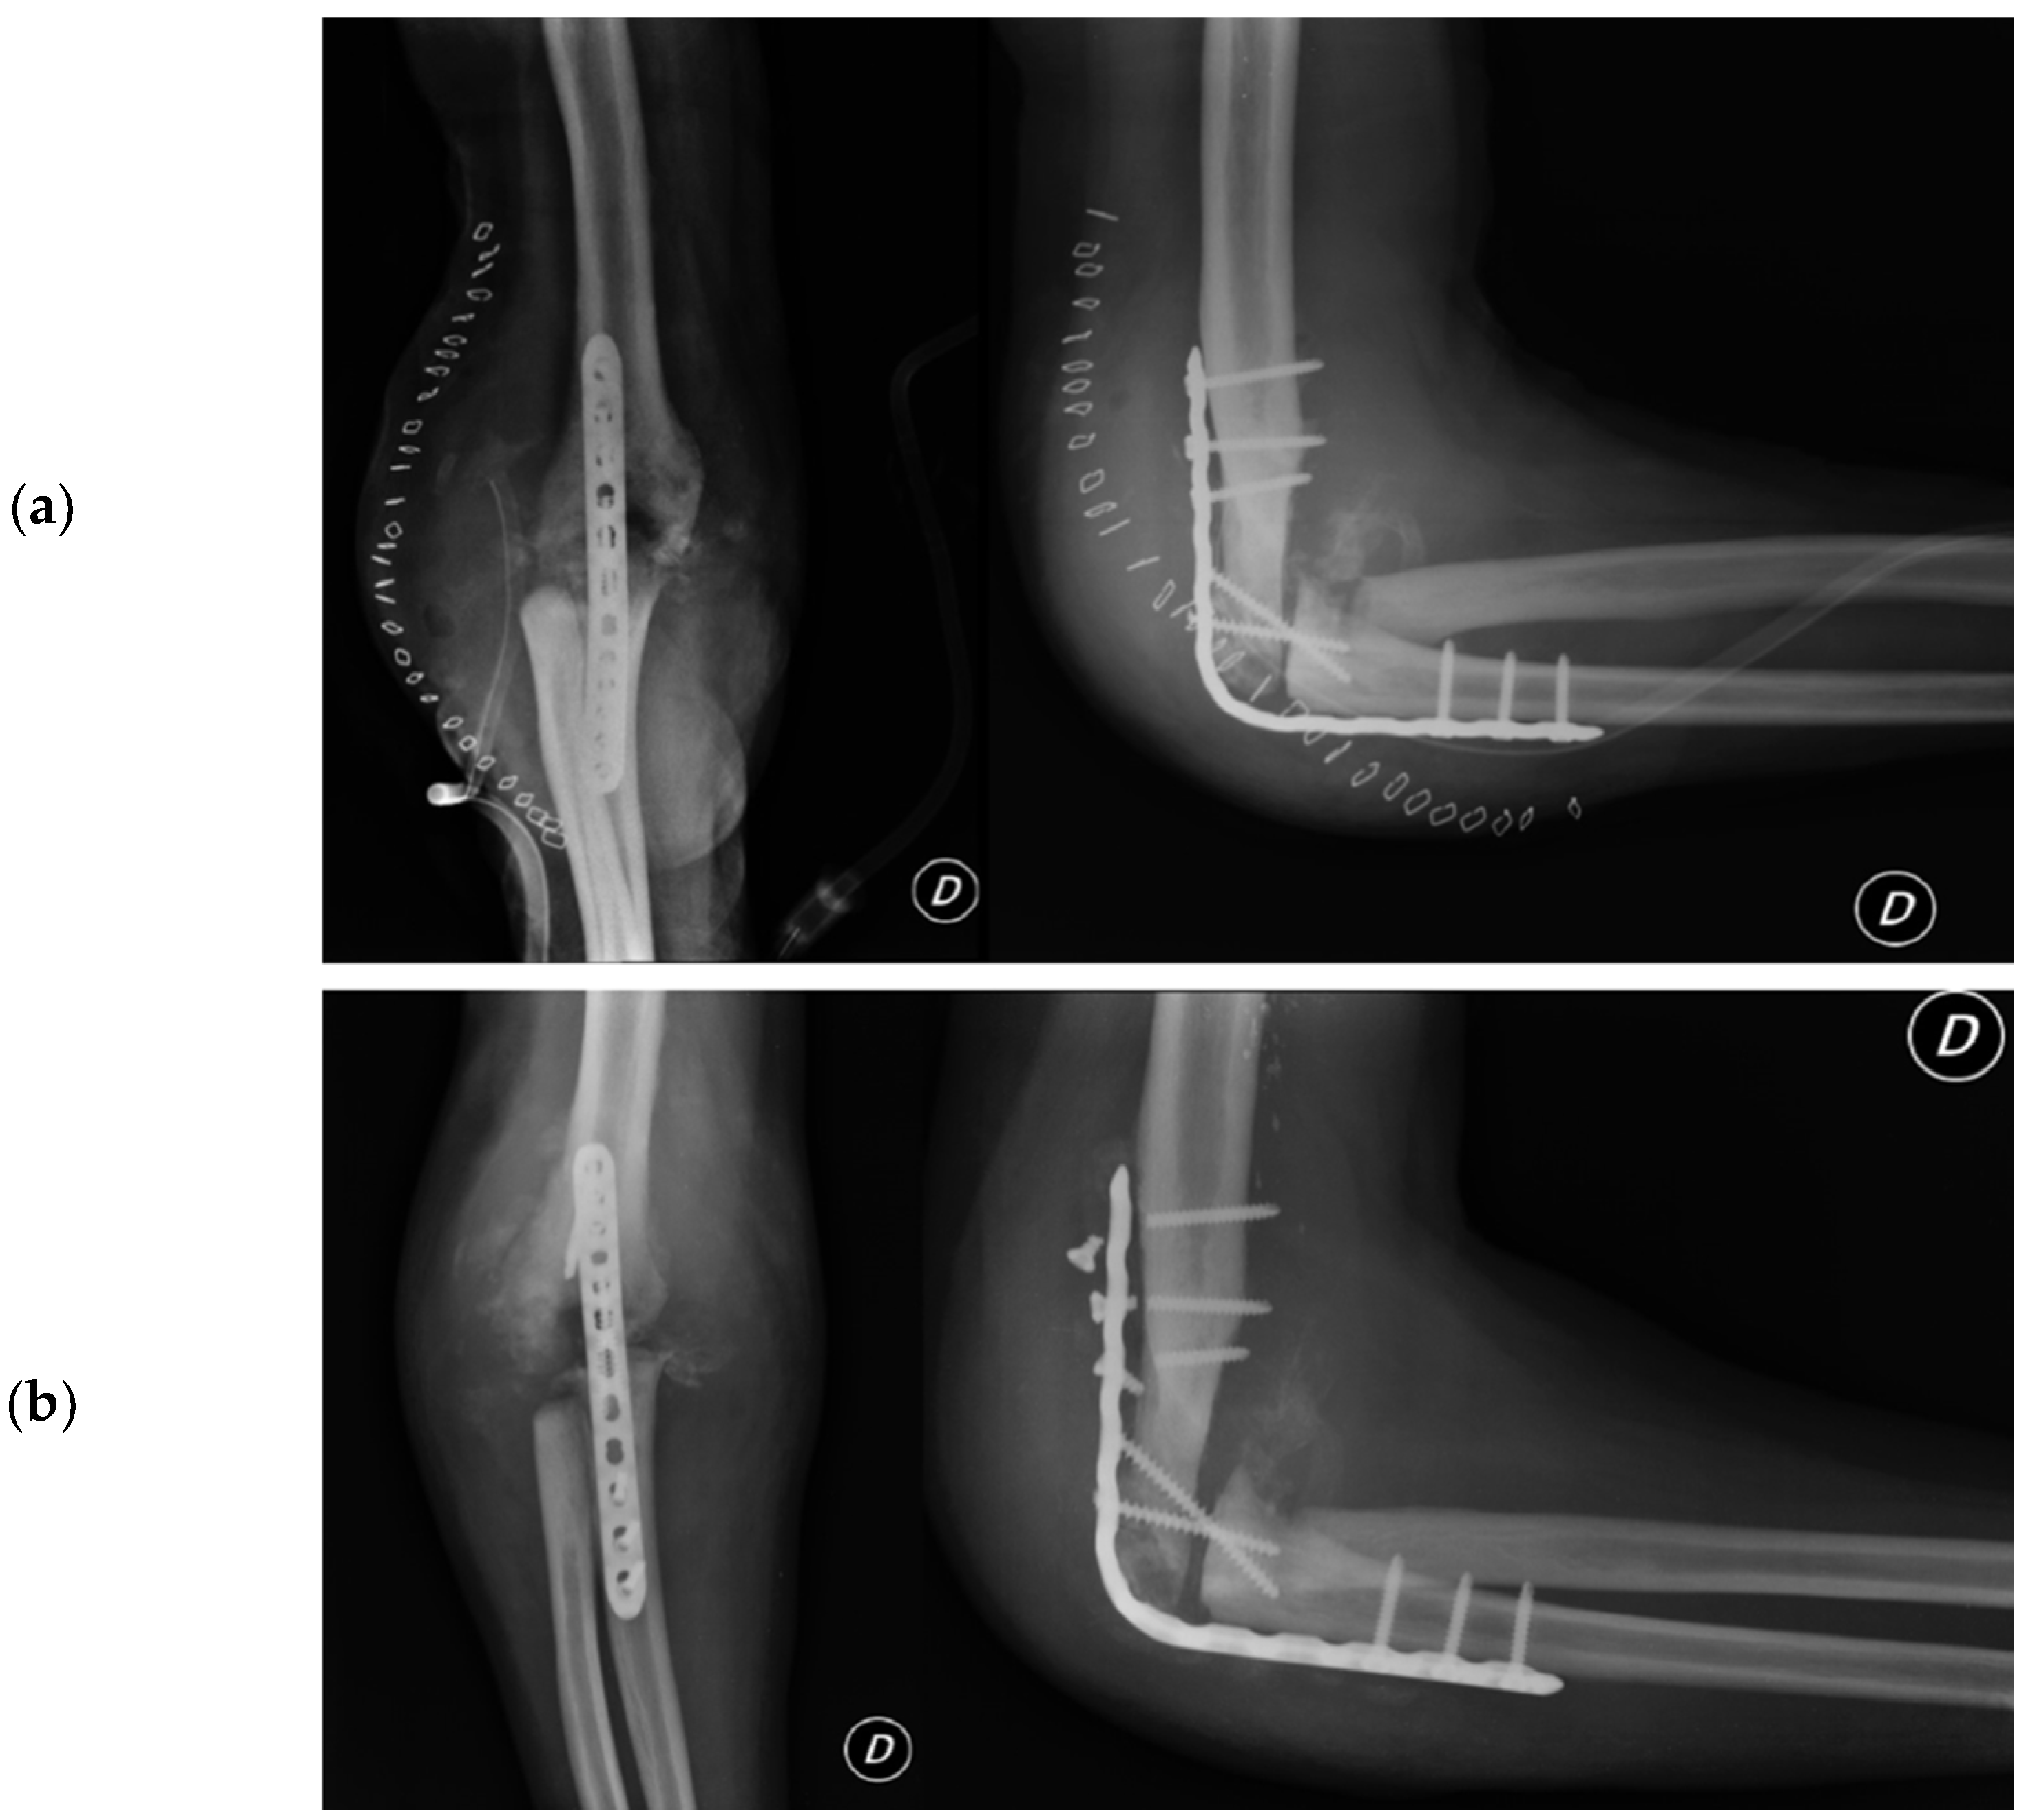

2. Case Presentation

2.4.5. Total Elbow Arthroplasty

- Evidence from the Scientific Literature

Total Elbow Arthroplasty and Complications